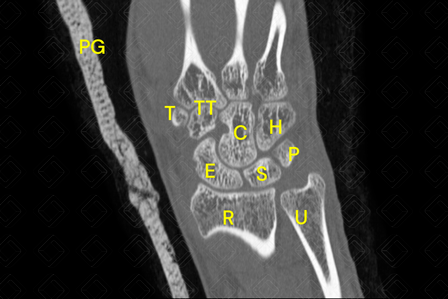

Texto alternativo para a imagem Figura 1. Créditos: Athena Hub/Medical Harbour

Legenda: C = capitato; E = escafoide; H = hamato; P = piramidal; [cms-watermark] [cms-watermark] [cms-watermark] [cms-watermark] PG = prótese gessada; R = rádio; S = semilunar; T = trapézio; TT = trapezoide; [cms-watermark] [cms-watermark] U = ulna.